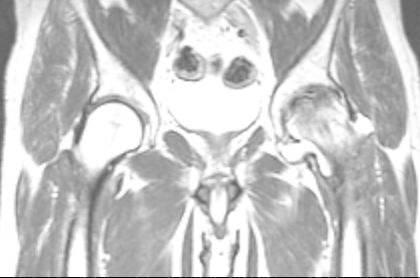

Avascular necrosis of the femoral head (AVN) is an increasingly common cause of musculoskeletal disability, and it poses a major diagnostic and therapeutic challenge. Although patients are initially asymptomatic, AVN usually progresses to joint destruction, requiring total hip replacement, usually before the fifth decade. Avascular necrosis is characterized by osseous cell death due to vascular compromise. Avascular necrosis of bone results generally from corticosteroid use, trauma, pancreatitis, alcoholism, radiation, sickle cell disease, infiltrative diseases (e.g. Gaucher's disease), and Caisson disease. The most commonly affected site is the femoral head and patients usually present with hip and referred knee pain. The aim of diagnostic imaging procedures in avascular femoral head necrosis is to provide the patient with a stage-adapted therapy. Therefore, a differentiated diagnostic work-up is needed. Native radiography of the hip in two planes is still the first step. Over the past years, the diagnosis of femoral head necrosis has experienced tremendous improvement due to the use of MRI and CT scans. Because of these improvements the correct stage can be diagnosed early and the appropriate therapy can be initiated immediately. Today, MRI is the most sensitive diagnostic imaging procedure. CT scans can be particularly useful to exclude subchondral fractures. The use of bone scintigraphy is restricted to exceptional cases. In Europe, the ARCO classification of avascular femoral head necrosis has been widely accepted. In this overview, we describe the specific characteristics of the different diagnostic imaging procedures and illustrate them with appropriate imaging material.

股骨头缺血性坏死(AVN)是导致肌肉骨骼残疾的一个日益常见的原因,它带来了重大的诊断和治疗挑战。尽管患者最初没有症状,但AVN通常会发展为关节破坏,通常在50岁之前就需要进行全髋关节置换。缺血性坏死的特征是由于血管受损导致骨细胞死亡。骨缺血性坏死通常由使用皮质类固醇、创伤、胰腺炎、酗酒、辐射、镰状细胞病、浸润性疾病(如戈谢病)和减压病引起。最常受累的部位是股骨头,患者通常表现为髋部疼痛并伴有膝关节牵涉痛。股骨头缺血性坏死诊断成像程序的目的是为患者提供适合其分期的治疗。因此,需要进行差异化的诊断检查。髋关节的双平面X线平片仍然是第一步。在过去几年中,由于使用了MRI和CT扫描,股骨头坏死的诊断有了巨大改善。由于这些改进,可以早期诊断出正确的分期,并立即开始适当的治疗。如今,MRI是最敏感的诊断成像程序。CT扫描对于排除软骨下骨折特别有用。骨闪烁显像的应用仅限于特殊情况。在欧洲,股骨头缺血性坏死的ARCO分类已被广泛接受。在本综述中,我们描述了不同诊断成像程序的具体特征,并用适当的影像资料进行说明。